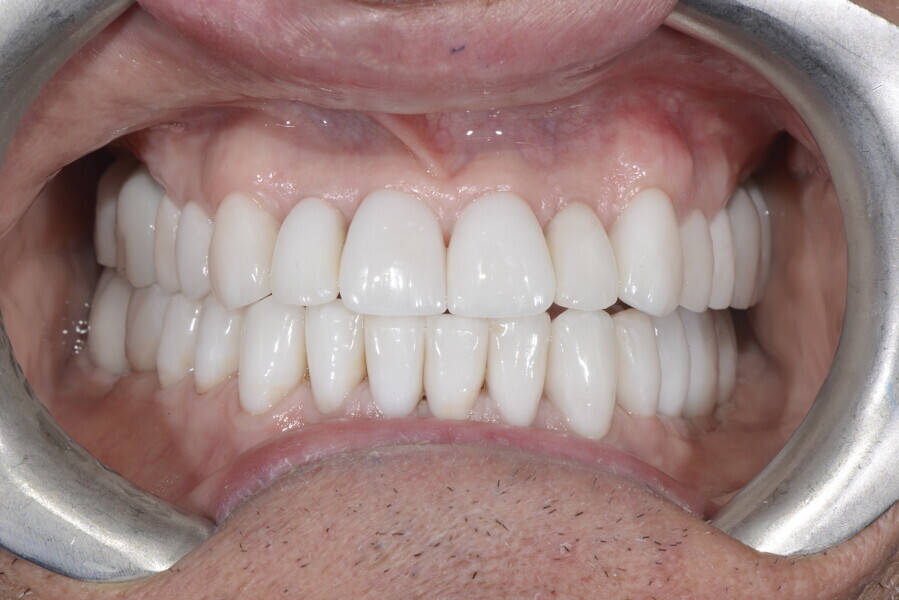

After the first phase of aligner treatment, we had achieved better inter-arch coherence, better maxillary arch expansion, and some space for improving the anterior tooth proportions restoratively (Fig. 19). We then temporarily restored the anterior teeth directly with composite, closing the spaces, improving the tooth proportions and further increasing the maxillary arch expansion (Fig. 20). We used restorative arch expansion to reduce the orthodontic destabilisation of the teeth to achieve the correct inter-arch coherence and retain the teeth in the cortical bone.38 A refinement aligner phase was undertaken to improve the final alignment of the gingival zenith and to improve the inter-arch coherence (Fig. 21). The periods of the first orthodontic phase and of the refinement were used to augment the mandibular and maxillary bone and to place the implants (Fig. 22). At the end of the orthodontic treatment, the case was finalised with ceramic veneers in the anterior area and temporary restorations on the implants in the posterior area (Figs. 23–26).

The provisional phase of about four months was important to allow the peri-implant tissue to mature and to teach the patient to chew correctly with chewing gum, cotton rolls and silicone masticatory sticks. This is fundamental training for the patient to achieve the correct alternating unilateral masticatory cycle needed to obtain the ideal rehabilitation of the masticatory system. We wanted the patient to achieve ideal masticatory and swallowing function. After sufficient rehabilitation time, we finalised the case with posterior zirconia crowns screwed on to the implants (Fig. 27).26

Our ideal final rehabilitation goals were:

• posterior stability;

• inter-arch coherence and U-shaped arches;

• anterior freedom during mastication;

• minimum disclusion vertical dimension;

• alternating unilateral masticatory cycle;

• physiological swallowing and high tongue posture against the palate; and

• mandibular disclusion advancing the mandible freely.

For maintenance purposes, after prosthetic finalisation, the patient was to carry on with the Froggymouth therapy and to use the Ri.P.A.Ra. for physiotherapeutic exercises and mastication training (Fig. 28). It was strongly recommended that the patient wear a mandibular occlusal splint during sleep. This occlusal splint was designed with disclusion guides to advance the mandible and ensure balanced contralateral support (Fig. 29).11, 39 We achieved an aesthetic appearance with adequate inter-arch coherence and a better cephalometric result (Figs. 30 & 31).